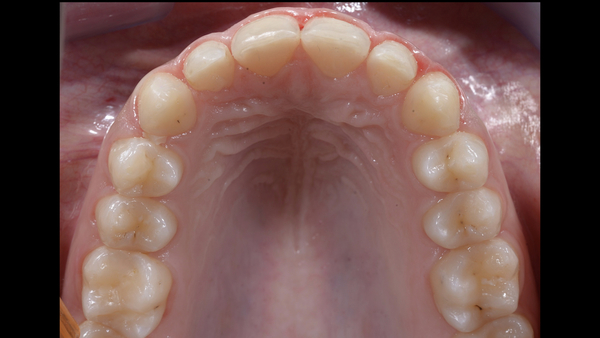

Fig. 10. I restauri appena cementati.